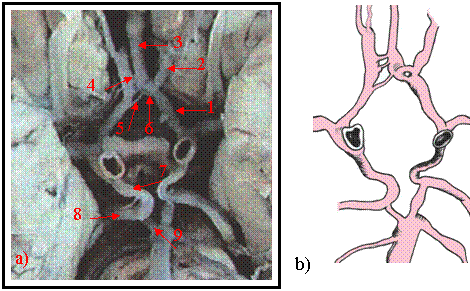

Cazul -2 [figura 9.2 a) si b)]

La acest caz artera cerebrala anterioara stanga in portiunea distala a segmentului A-1 apare sub forma unei trifurcatii, prezentand o ramura laterala si doua ramuri mai subtiri cu orientare mediala. Ramura laterala, bine calibrata, urmeaza traiectul segmentului A-2 al arterei cerebrale anterioare. Ramurile mediale se anastomozeaza, formeaza o butoniera vasculara si se continua sub forma de artera cerebrala mediana. Inchiderea poligonului Willis in partea anterioara se realizeaza prin mai multe artere comunicante anterioare de calibru redus, avand dispozitie scalariforma

Figura 9.2 a) vasele poligonului Willis disecate pe encefal

b) prezentare schematica

1-.segmentul A-1 al cerebralei anterioare stangi. 2.-.segmentul A-2 al cerebralei anterioare stangi. 3-.artera cerebrala anterioara mediana. 4.-artere comunicante anterioare. 5- prima comunicanta anterioara. 6.- butoniera arteriala. 7.- comunicanta posterioara. 8.- segmentul P-2 al cerebralei posterioare drepte. 9.-.segmentul P-1 al cerebralei posterioare drepte.

Prima comunicanta, mai lunga, realizeaza anastomoza intre artera cerebrala anterioara dreapta cu prima portiune din ramificatia cerebralei anterioare stangi. Urmatoarele trei comunicante anterioare, foarte scurte, realizeaza anastomoza cerebralei anterioare drepte cu artera cerebrala mediana. In sectorul posterior al poligonului arterele comunicante posterioare aproape simetrice, de calibru peste mediu, se continua cu segmentul P-2 al cerebralei posterioare. Segmentul P-1 al cerebralei posterioare, de lungime redusa bilateral, ramane ca o punte anastomotica intre trunchiul arterial bazilar si artera comunicanta posterioara.